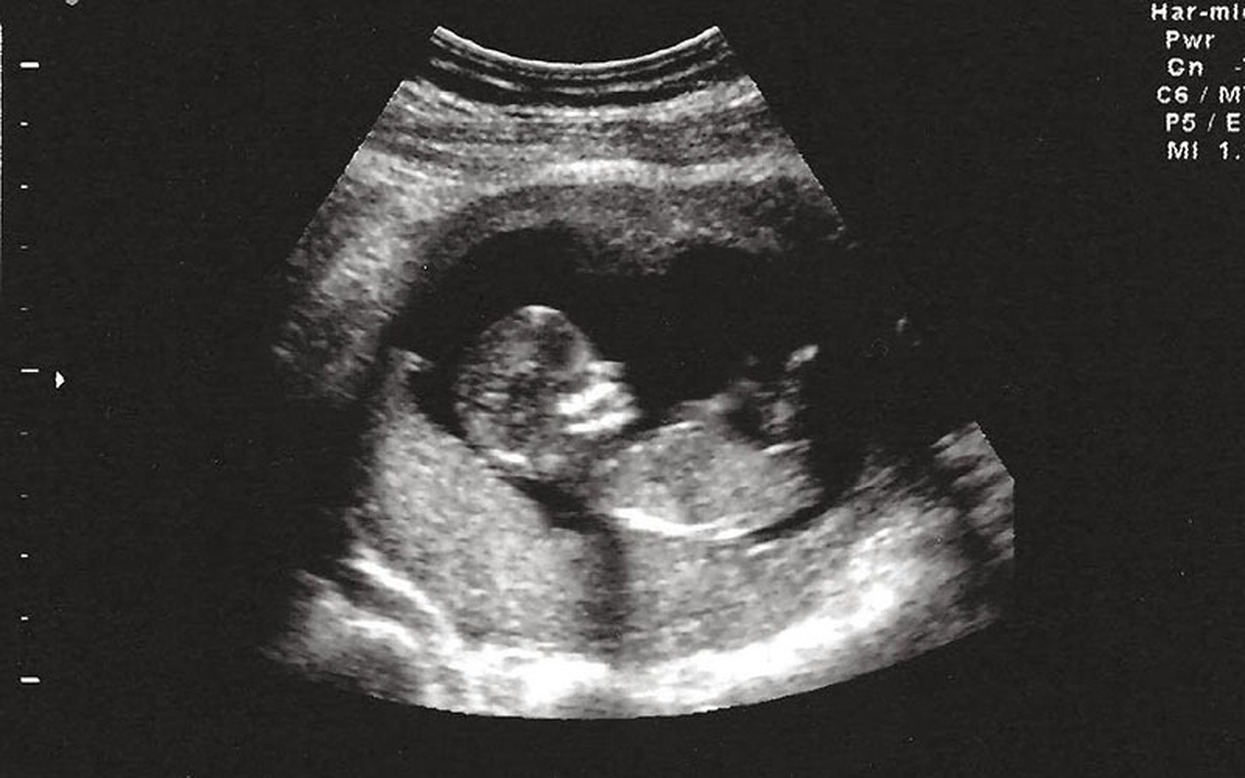

4 năm hôn nhân, 5 lần mang thai nhưng đều mất con, người phụ nữ đau khổ nhìn chồng cũ lấy vợ mới- Ảnh 2.

4. Xét nghiệm sàng lọc thai kỳ (sau khi đã mang thai)

Bao gồm: Double test, Triple test, NIPT, siêu âm hình thái, v.v.

Nếu có nghi ngờ bất thường, bác sĩ sẽ chỉ định thêm xét nghiệm di truyền chuyên sâu hoặc xét nghiệm gen của bố mẹ.